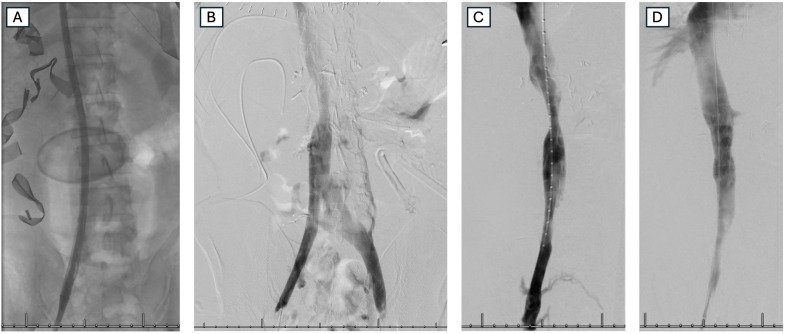

We describe the surgical dilemma of an adult male who arrived with a penetrating injury to the suprarenal inferior vena cava (IVC), where conventional intraoperative hemorrhage control failed. Our team innovated by using an atriocaval shunt for temporization of the injury during resuscitation, enabling us to return to the operating room and perform primary repair. Notably, the prolonged use of the atriocaval shunt as a damage control strategy represents a novel application, as it remained in place for several hours-a first in reported cases. We detail this technique, the multidisciplinary approach to managing concomitant severe injuries, and the resulting complications and outcomes. This case highlights the challenges of managing suprarenal IVC injuries and demonstrates the potential role of prolonged atriocaval shunting as a damage control strategy.